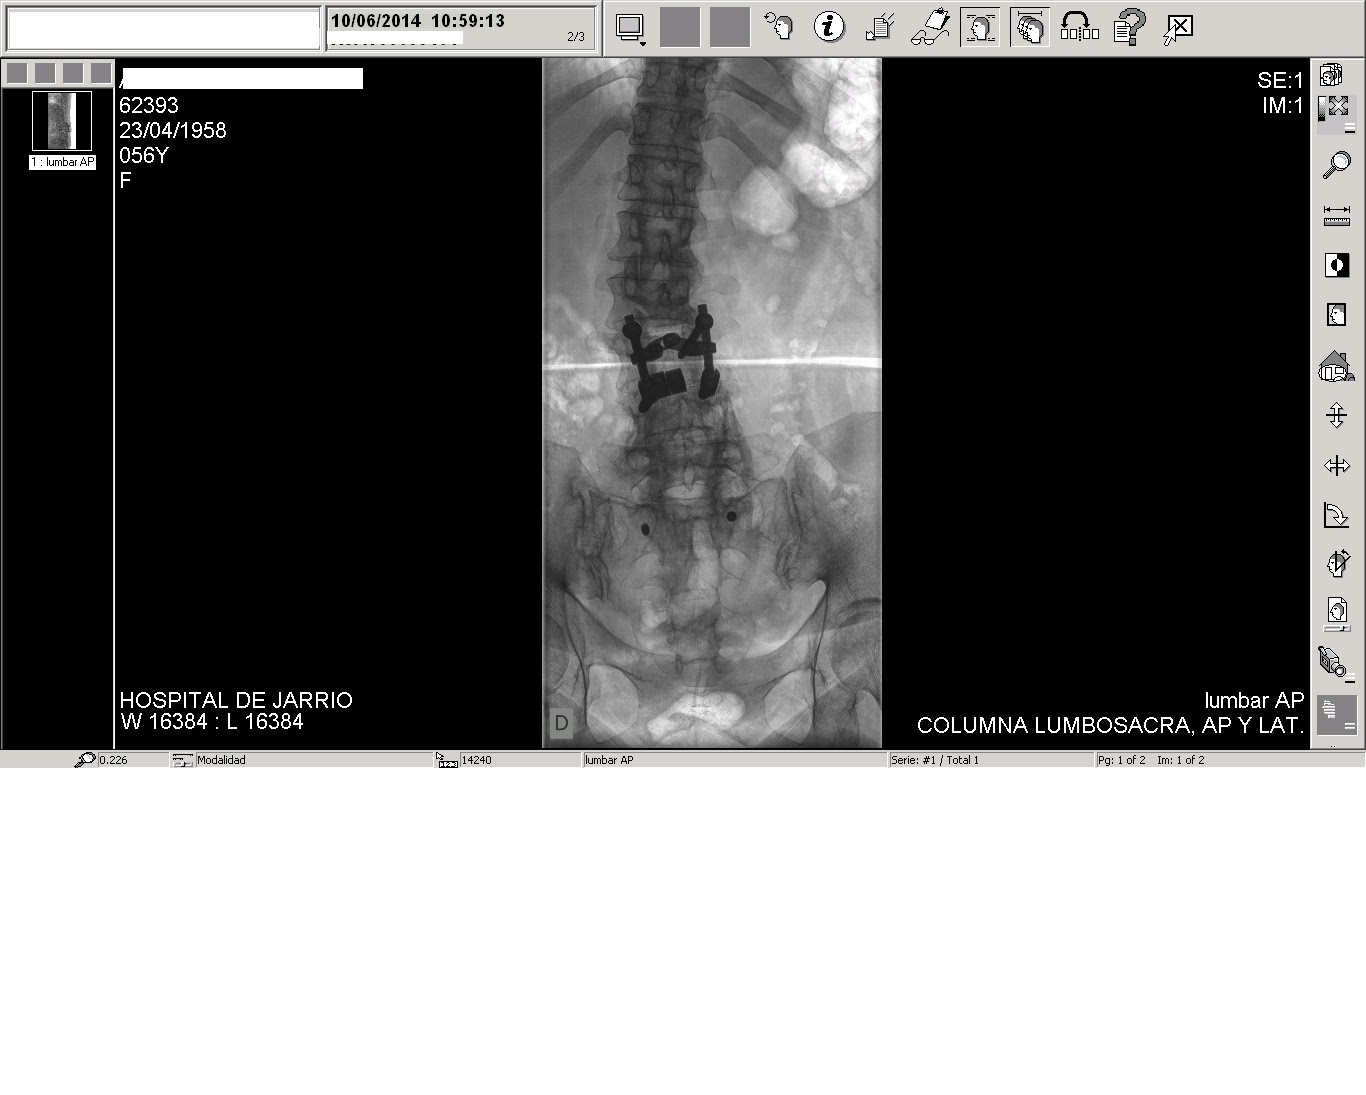

Fotografias de la cirugia: Artrodesis lumbar posterolateral instrumentada

Source: www.cirugiaarticular.com